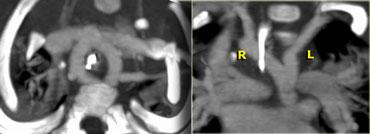

Right Arch with Aberrant left subclavian

The Right Aortic Arch with an aberrant left subclavian is an obstructing arch anomaly.

The first branch of the aorta is the left common carotid, followed by the right subclavian artery and the left common carotid.

This also is a true ring.

The ligamentum ductus arteriosus between the arch at the level of the left subclavian artery and the left pumonary artery completes the ring.

If this ligament is very short, there will be a lot of compression.

On the left a patient with a right arch with an aberrant left subclavian (indicated by the yellow arrow).

There is a right arch and the left subclavian artery is the last branch of the aortic arch, indicating that this is an aberrant left subclavian.

Medially to the left subclavian artery we see the left common carotid, that originates from the right side and has an oblique course to the left.

Same patient.

Posterior oblique view of volume rendered image to show the aberrant left subclavian artery.

In a mirror type right arch, the left subclavian is the first brach and forms the left innominate together with the left common carotid.

On the left images of a symptomatic child.

On the axial image there is a right arch with the left subclavian artery that comes off on the posterior side and runs behind the trachea and the esophagus.

The compression of the trachea is demonstrated on the volume rendered view.